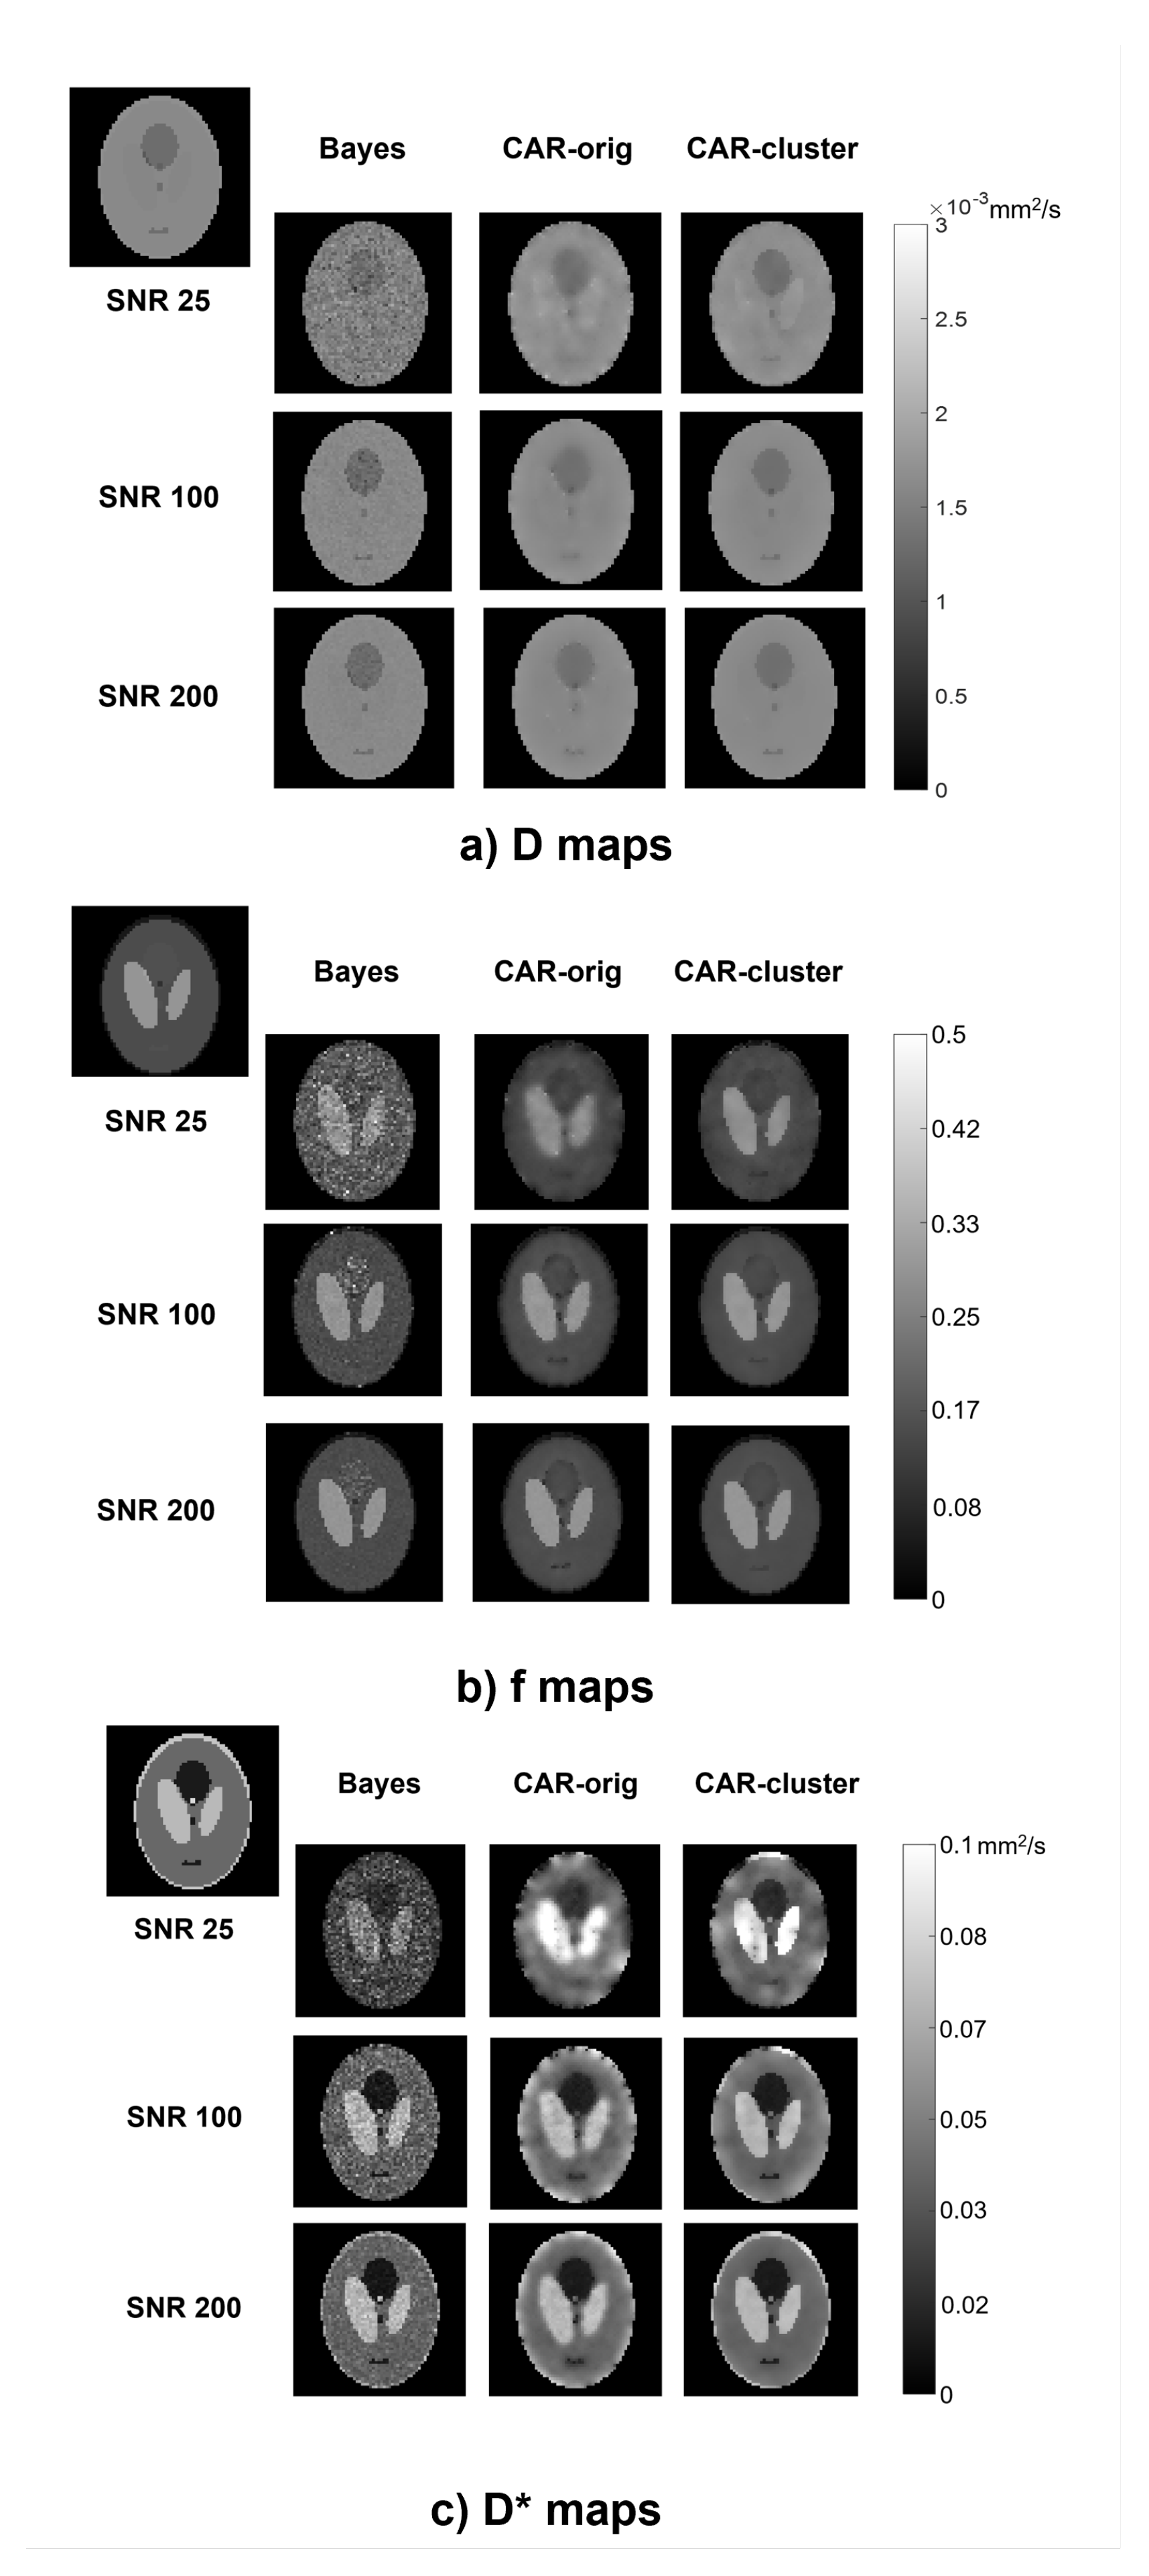

The qualitative comparison of the estimated maps among the three different methods revealed that the CAR clustering approach was able to improve their quality with respect to the Bayesian CAR method without clustering and the state-of-the-art Bayesian approach without CAR (Figure 2).

Figure 2. Parametric maps of D (a), f (b) and D * (c), estimated from a simulated image using the three methods (columns) at different S N R values (rows). The true maps are also reported in the top left corner.

The Bayesian estimation without CAR generated maps with high contrast between different structures, but maintained a certain level of noise throughout the image, especially at low S N R values. On the contrary, the CAR approach without clustering was able to generate homogeneous values within the ROIs, but at the same time it lost the boundaries between the regions and introduced blurring and blotchy artifacts, especially at low S N R values and for D * . Instead, the proposed approach with clustering better highlighted the contrast between structures at the interfaces, and preserved a high homogeneity within the regions; therefore, it retained the advantages of both other methods.